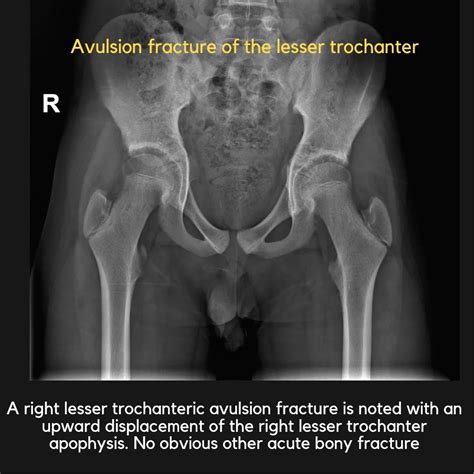

Avulsion Fractures

Avulsion fracture of the lesser trochanter occur when the iliopsoas sinew pulls off from the bone, taking a sherd of the less trochanter with it. These injuries are typically seen in adolescents and young adults who enter in sports that involve sudden, forceful hip flexure, such as soccer, basketball, and track and field. Avulsion fractures can cause hurting, swell, and trouble with hip flexion and weight-bearing action.

Imaging studies: X-rays, magnetic plangency imaging (MRI), and compute tomography (CT) scans can help project the lesser trochanter and besiege construction. These image work can identify fracture, inflaming, and other abnormality.

Case Study 1: Avulsion Fracture in a Soccer Player

A 16-year-old male soccer musician represent with sudden onset of inguen hurting during a game. He reported feel a "pop" in his groin area and was ineffectual to proceed acting. An X-ray revealed an avulsion fracture of the lesser trochanter. The instrumentalist was treated guardedly with rest, ice, compression, altitude (RICE), and physical therapy. He gradually return to soccer after six workweek and made a total retrieval.